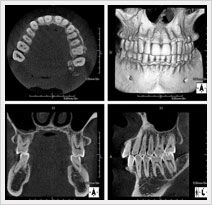

顎の形態・性状だけでなく、神経・血管の走行、上顎洞(鼻の奥)の形態や粘膜の状態、病巣などを立体画像で確認することができます。

インプラントだけでなく、矯正や根管治療、親知らずなど、幅広く歯科治療に応用することができ、正確な診査・診断により、治療の安全性を高めます。

インプラントを埋める部位の骨の質や厚み・形態、神経・血管の位置が正確に分かり、確実な診断が可能となります。また必要な場合には、手術中にもCT撮影ができることで、インプラントの位置や方向などの確認ができ、より安全・正確にインプラント手術をすることができます。